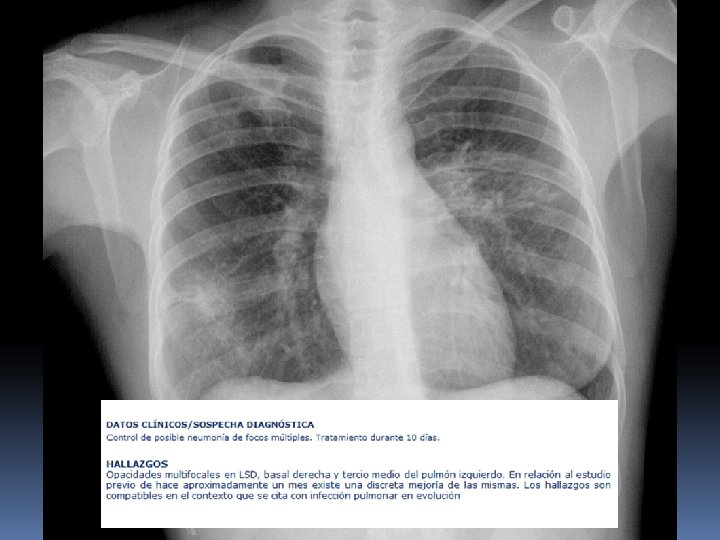

Un mes mas tarde……. .

2008 2013